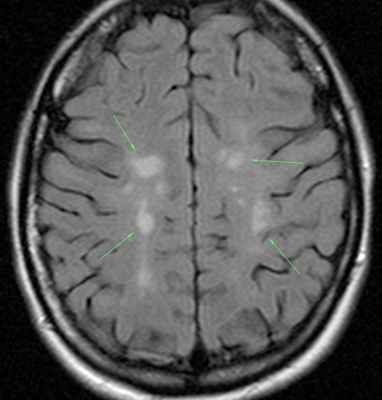

Как распознают рассеянный синдром на снимках? При рассеянном склерозе на снимках заметно характерно типичное распределение очагов в белом веществе головного мозга. Кроме того, для данного диагноза характерно поражение мозолистого тела, дугообразных волокон, височных долей, мозгового ствола, мозжечка и спинного мозга. Такое распределение очагов нехарактерно для иных патологических процессов, поэтому трудностей при постановке диагноза обычно не возникает. При ангиопатии возможны поражения ствола мозга, однако они обычно симметричны и располагаются центрально, в то время как очаги при рассеянном склерозе локализованы по периферии.

Поэтому, когда пациенты задают вопрос, видно ли на МРТ рассеянный склероз, то можно дать вполне конкретный ответ. Зоны поражения отображаются как ярко-белое пятно либо затемненная область. Вариант визуализации зависит от типа МРТ, который вам подберут индивидуально.

На изображениях, получаемых посредством МРТ при рассеянном склерозе, диагност четко видит:

- более интенсивный сигнал, что на картинке выражено наличием очага или очагов

- общее количество очагов

- расположение очагов и их близость к важным структурам головного мозга.

Основные признаки РС:

- Обнаружение очагов демиелинизации в церебральных структурах является безусловным подтверждением диагноза PC.

- При ремиттирующих формах РС на ранних этапах отмечается наличие большего количества очагов крупных размеров, локализующихся в функционально значимых анатомических структурах, включающих ствол, мозжечок. На ранних сроках заболевания при этом типе течения наблюдается расширение желудочков и субарахноидальных цистерн.

МРТ критериями обострения PC служат следующие признаки:

- образование новых и повторное появление исчезнувших очагов;

- увеличение в размерах уже существующих очагов.